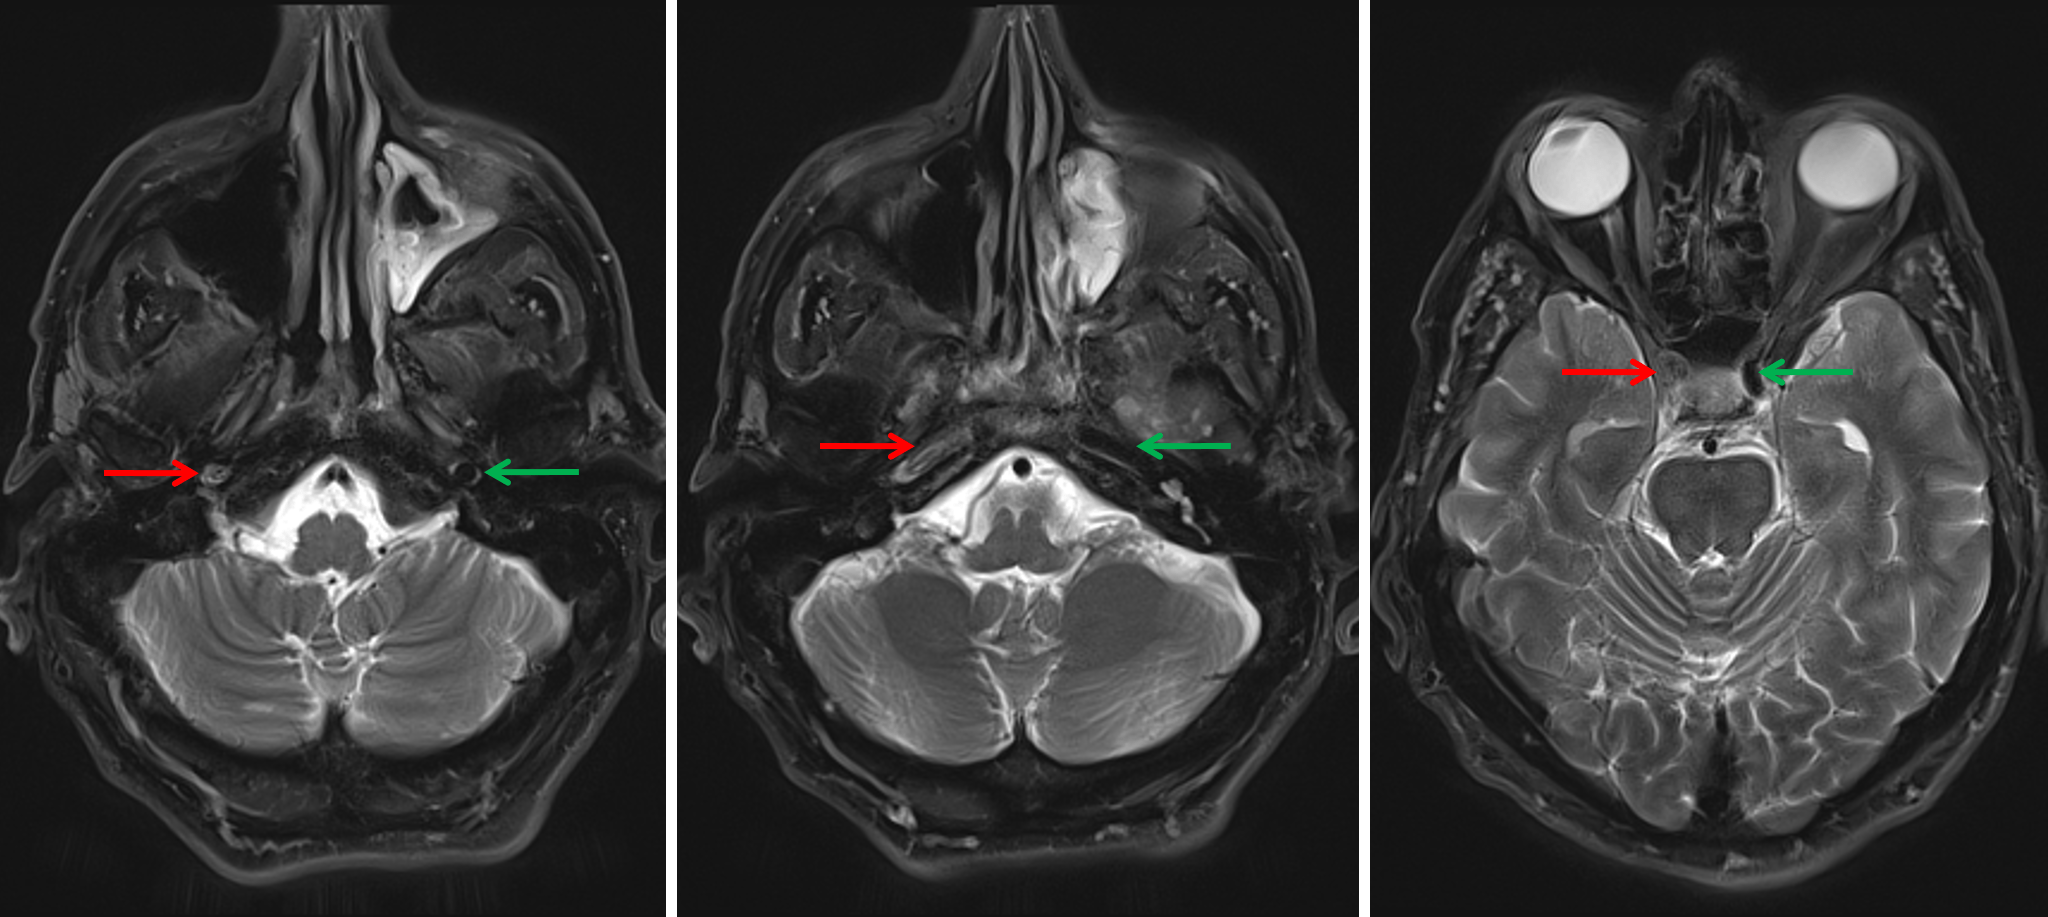

Signal Loss and Asymmetry Download Scientific Diagram Signal Loss Mri Potential causes are diverse, including traumatic,. Susceptibility weighted imaging (swi) is an mri sequence that is particularly sensitive to compounds which distort the local. Dephasing of spinning protons (loss of resonance) two types of signal can be detected; Diffuse t1 vertebral bone marrow signal loss is associated with replacement of fatty marrow by edema or cellular tissue. T1 signal relates. Signal Loss Mri.

The FLAIR MRI sequence showed an area of signal loss in the left Signal Loss Mri Abnormal signal intensity within skeletal muscle is frequently encountered at magnetic resonance (mr) imaging. On mri, disc degeneration manifests as loss of the normal t2 hyperintense signal of the central nucleus pulposus and loss of disc height. Dephasing of spinning protons (loss of resonance) two types of signal can be detected; Potential causes are diverse, including traumatic,. Susceptibility weighted imaging. Signal Loss Mri.

T2 weighted resonance imaging (MRI) image of the orbits. Nine Signal Loss Mri On mri, disc degeneration manifests as loss of the normal t2 hyperintense signal of the central nucleus pulposus and loss of disc height. Diffuse t1 vertebral bone marrow signal loss is associated with replacement of fatty marrow by edema or cellular tissue. Disc degeneration leads to the development of. Susceptibility weighted imaging (swi) is an mri sequence that is particularly. Signal Loss Mri.